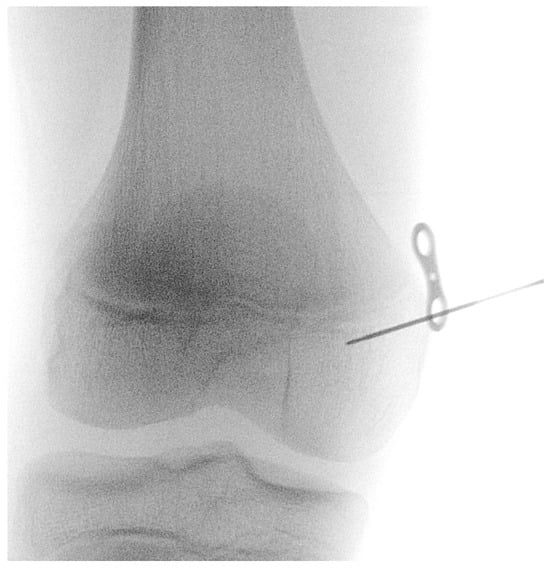

2.2. Surgical Technique